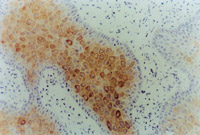

MEBT/MEBO治療30天后,再生修復(fù)的上皮組織進(jìn)行細(xì)胞角質(zhì)素AE3檢查為陽(yáng)性,表皮顆粒層細(xì)胞質(zhì)呈棕色染色,細(xì)胞核呈藍(lán)色(圖5-3-9~5-3-6),證實(shí)為自身再生的復(fù)層鱗狀上皮。

5-3-9 MEBT/MEBO治療30天,細(xì)胞角質(zhì)素AE3呈陽(yáng)性。(說明患者燒傷創(chuàng)面是自我再生修復(fù)) HE×20

5-3-10 同上  HE×40